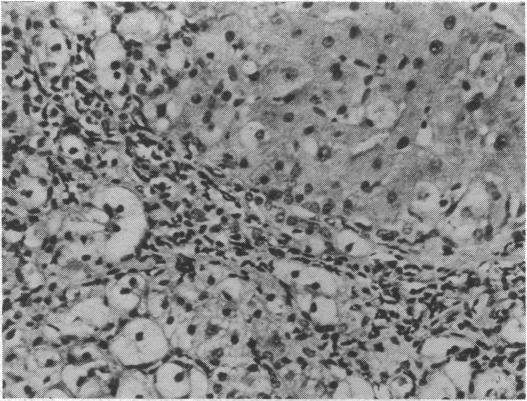

Histopathological findings in 91 Ugandan patients with cirrhosis were studied in relation to serological tests for the hepatitis-associated antigen (H.A.A.) and antibody (anti-H.A.A.). H.A.A. was present in 30 (32.9%) of the 91 patients as opposed to 7 (3.1%) out of 224 controls drawn from the same population (P<0.001). Younger subjects and males were more frequently positive. There was no difference in the presence of anti-H.A.A. between patients and controls. Correlation of the results of serological testing with histopathological features showed that macronodular ("posthepatitic," "postnecrotic") types of cirrhosis, which predominate in Uganda, were associated with the presence of H.A.A. but that the much less common micronodular ("nutritional," fatty, portal) type of cirrhosis was not. Evidence was found, on the other hand, for a direct role of alcoholism in the latter. Detailed histological analysis also showed two types of cellular change-liver cell swelling and dysplasia-to be associated with the presence of H.A.A. The data suggest an aetiological role for H.A.A. in most cases of cirrhosis in Uganda and these may be identified by histological criteria.

对91例乌干达肝硬化患者的组织病理学检查结果进行了研究,并与肝炎相关抗原(H.A.A.)和抗体(抗H.A.A.)的血清学检测结果相关联。91例患者中有30例(32.9%)检测到H.A.A.,而从同一人群中抽取的224名对照者中只有7例(3.1%)检测到(P<0.001)。年轻受试者和男性的阳性率更高。患者和对照者之间抗H.A.A.的存在情况没有差异。血清学检测结果与组织病理学特征的相关性表明,在乌干达占主导地位的大结节性(“肝炎后”、“坏死后”)肝硬化类型与H.A.A.的存在有关,但不太常见的小结节性(“营养性”、脂肪性、门脉性)肝硬化类型则无关。另一方面,有证据表明酗酒在后者中起直接作用。详细的组织学分析还显示,两种细胞变化——肝细胞肿胀和发育异常——与H.A.A.的存在有关。数据表明,H.A.A.在乌干达大多数肝硬化病例中具有病因学作用,这些病例可以通过组织学标准来识别。